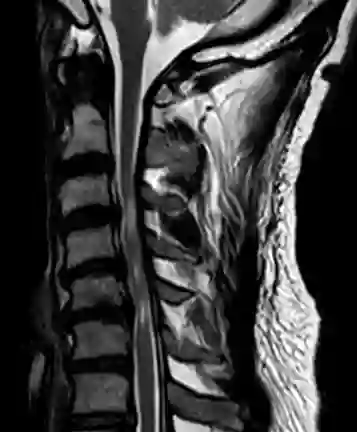

Zervikale Myelopathie MRT

Sagittale T2 Sequenz eines Patienten mit einer mutlisegmentalen zervikalen Myelopathie.